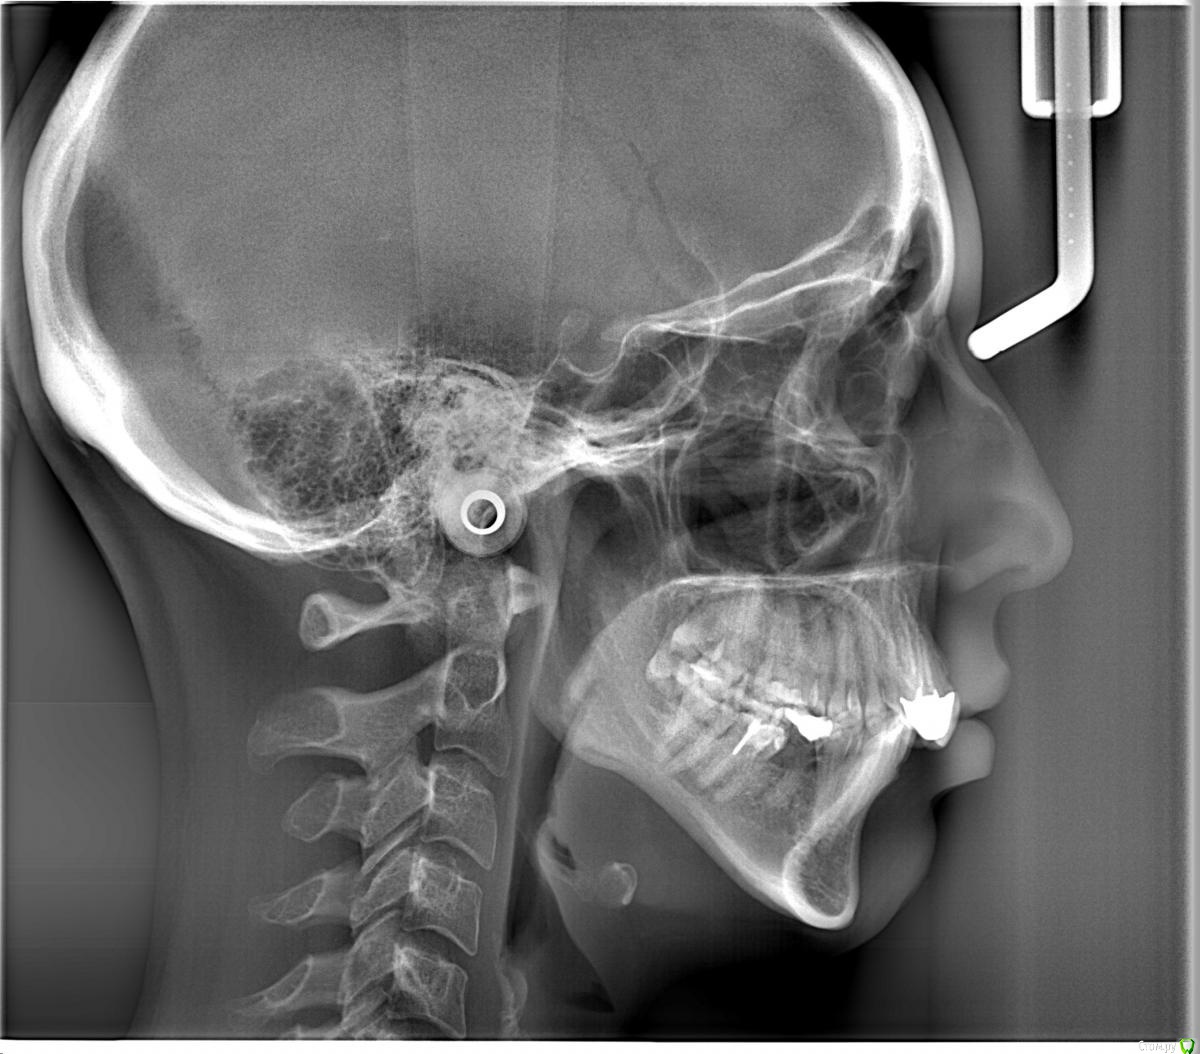

Oksanater Опубликовано 22 июня, 2016 Поделиться Опубликовано 22 июня, 2016 Здравствуйте.У меня глубокий дистальный прикус. Ноет правый суглоб. После некоторого изучения проблемы, я решила все таки обратится в клинику, где в стоматологии работает остеопат. Выбрана тактика остеопатического выдвижения нижней челюсти вперед совместно с ношением капы ночью. Предварительно ориентируются на 2 месяца такого лечения (мне 34 года). После этого в плане брекеты на верхнюю и нижнюю челюсть, которые переместят зубы в правльное положение, и возможно протезирование боковых зубов, где будет сильная диокклюзия.Что меня смущает. И что прошу проккоментировать:на первом приеме был сделан только слепок для капы, но остеопат "вставил челюсть" и отпустили домой, до следующего приема через две недели, когда дадут капу. Челюсть действительно подалась вперед, даже на следуещее утро пришлось ехать к стоматологу чтоб спилить коронки на верхних резцах, т.к. они поставлены взамен крывых своих зубов и сделаны намного толще (видимо чтоб создать типа смыкание с нижнимы зубами). Нижние резцы стали ударятся о верхние, но после обпиливания стало лучше. По прошествию суток чувствую, что челюсть все равно потихоньку занимает прежнее положение.У меня возникло опасение по поводу такого лечения. Не будет ли только ночное ношение капы просто расшатывать суглобы, не приведя к стойкому выдвижению?Если в моем вопросе помимо снимков все же нужны фото, то сделаю. Пока не делаю, т.к. после "вправления" как-то странно закрываю у "укладываю" зубы и очень напряжены мышцы нижней трети лица. Ссылка на комментарий

m.d.n Опубликовано 22 июня, 2016 Поделиться Опубликовано 22 июня, 2016 реконструкция оклюзионной плоскости нужна.выкладывайте фото .Так же кт суставов нужно , и гипсовка в артикулятор Ссылка на комментарий